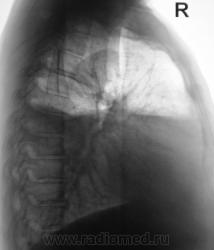

Признаков пневмоторакса по прямой R-грамме не нахожу( в наружном отделе среднего поля справа, явно не воздух т.к.тень значительно плотнее лёгочной ткани), по боковой проекции действительно видна жидкость с горизонтальным уровнем-может быть этот уровень имеет отношение к средостению? Случай непростой, нужна клиника и анамнез.

Уровень сохраняется горизонтальный за счет осумкования так как не растекается на томограммах.Пневмоторакс сомнителен. А вот причина плеврита ?

- вызывает сомнение полоса просветления в мягких тканях гр. клетки справа, там где стрелка виднеется;

О пневмотораксе говорит светлая полоса по краю легочного поля справа - там и не прослеживается легочной рисунок.(Во всяком случае на моём мониторе.